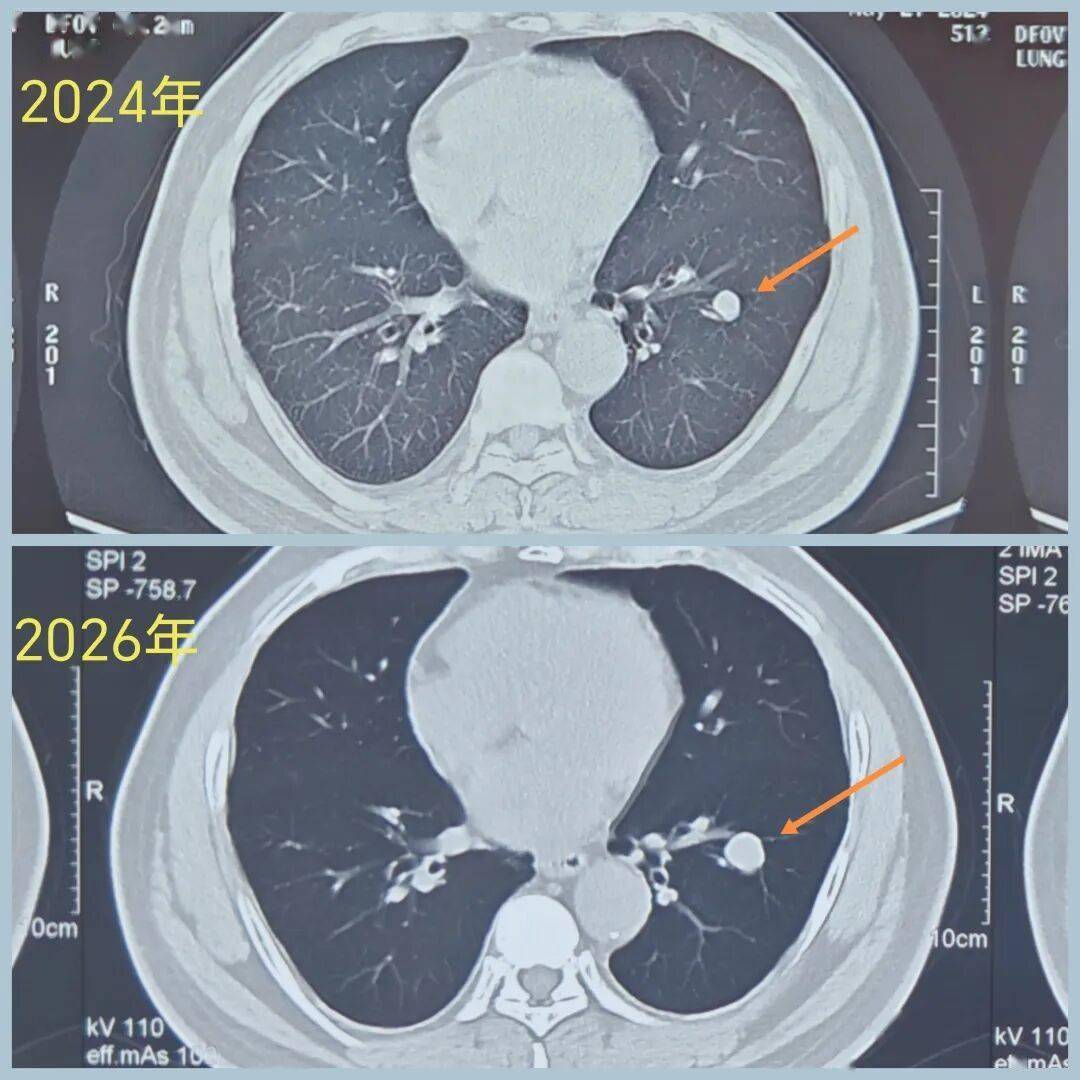

【病例2】

男性,40+岁,发现左下叶实性结节5年

患者诉结节刚发现时为0.8cm,形态像良性,给予定期复查

后结节 逐渐增大

2026年3月CT示病变1.6cm

虽然病变像良性,但一直在增大,不能除外肺癌,因此有手术指征。

(再早片子无法追溯,只能对比24年的片子。)

术前CT示:左肺下叶基底段实性结节,大小1.6cm,边界清,有浅分叶,内部密度不均,有点状高密度。看形态确实像良性。